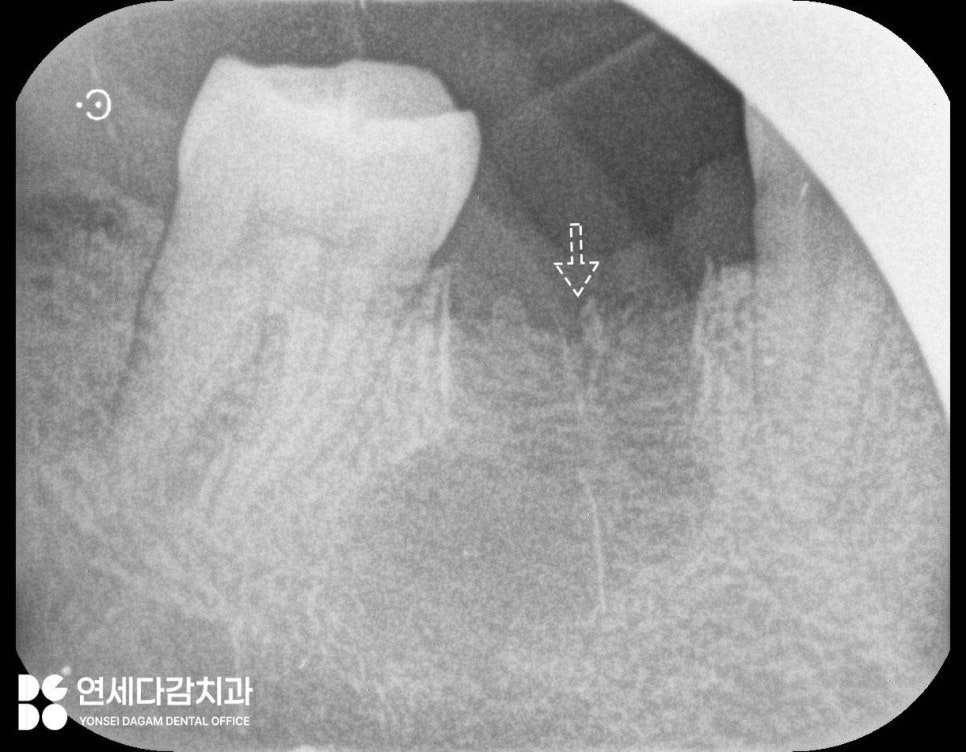

엑스레이 촬영을 하면 투과성으로

치아 뿌리 끝에 검은 그림자처럼

나타나는 것이 특징입니다.

치근단낭이 깔끔하게 적출된 모습

이를 뺀 발치와 부위를

깨끗하게 긁어내는 소파(curettage)

과정이 꼼꼼하게 진행되어야

발치 후 회복이 원활하게 진행되고

재발을 방지할 수 있습니다.

술 후에는 치근단 촬영을 통해

꼼꼼하게 확인한 후

소독하여 마무리하게 됩니다.